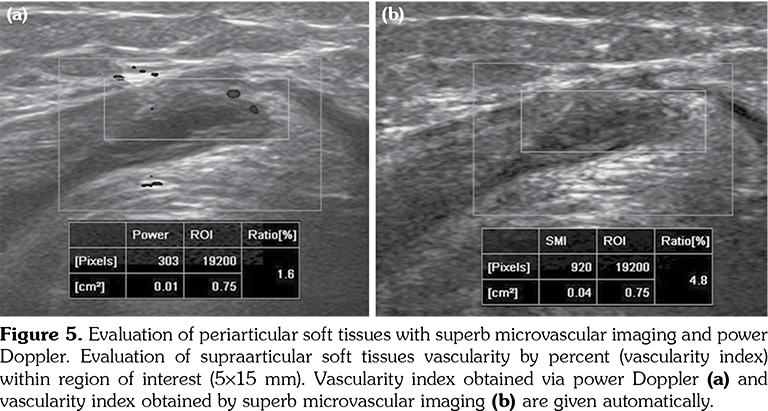

All patients and healthy volunteers were screened with Canon Aplio 500 Platinum US device (Canon Medical Systems, Tokyo, Japan) equipped with SMI, PD and SWE functions. All participants were examined in supine position and their knees were in extension (Figures 1, 2). Once the gray scale US examination confirmed the arthritis based on synovial thickening, joint effusion and periarticular echogenicity, then SMI and SWE were performed to the supraarticular and infraarticular soft tissues concerning the synovium and periarticular soft tissues. VI is a novel parameter determined for SMI and PD corresponding the ratio of colored pixels to the total pixels within the selected region of interest (ROI). VI was calculated automatically on colored SMI and PD images over the selected rectangular shaped ROI with edges measured 5x15 mm (Figure 3). Mean VI values were calculated by averaging results of three different acquisitions of PD and SMI. The ROI was placed perpendicular to the long axis of the knee joint at the supraarticular and infraarticular locations including the synovium and periarticular soft tissues. On SWE evaluation, the QT and PT were demonstrated along with their long axis. Three different ROIs for SWE were performed from the tendon halves closer to the knee joints. Each ROI was in circle shape and 3 mm in diameter. We depicted mean elasticity for PT, QT, supraarticular soft tissues (SAST) and infraarticular soft tissues (IAST) (Figures 4, 5).

No statistically significant difference was found between the mean ages of study and control subjects. Mean VI values in the study group obtained from SAST including synovium and suprapatellar fat pad were 8.2±3.4% for SMI and 9.1±3.1% for PD. Those were found as 2.9±1.4% for SMI and 3.4±1.4% for PD in the control group. When the study and control groups were compared, there was a statistically significant difference between VI values determined by SMI (p<0.001) and PD (p<0.002), respectively. In the study group, mean VI values obtained from IAST including synovium and infrapatellar fat pad were 7.9±3.1% for SMI and 8.1±2.8% for PD. Those were found as 2.6±1.5% for SMI and 3.1±1.5% for PD in the control group. There was a statistically significant difference for VI values of IAST via SMI (p<0.001) and PD (p<0.003) among the study and control groups, respectively. A comparison of overall VI values obtained from both study and control group participants did not show any statistically significant difference among mean values (p>0.05).